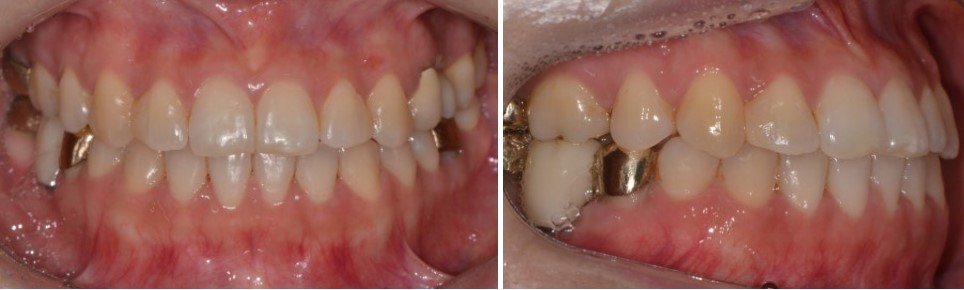

윗니 치열 폭경 확장

위 치열의 폭을 넓혀

윗니가 아래 치아를 더 안정적으로 감쌀 수 있도록 조정했습니다.

아랫니 전체를 뒤로 이동

교정용 스크류를 이용해

아랫니 전체를 후방으로 이동시키는 치료를 진행했습니다.

약 1년 6개월에 걸친 꽤 긴 치료 기간이 필요했지만,

그 결과 올바른 교합 관계가 형성되었습니다.

옆모습 역시,

수술을 한 것처럼 드라마틱하게 변하는 것은 아니지만,

교합이 안정되면서 아랫입술이 자연스럽게 뒤로 들어가고,

얼굴 인상이 한결 편안해진 것을 확인할 수 있었습니다.